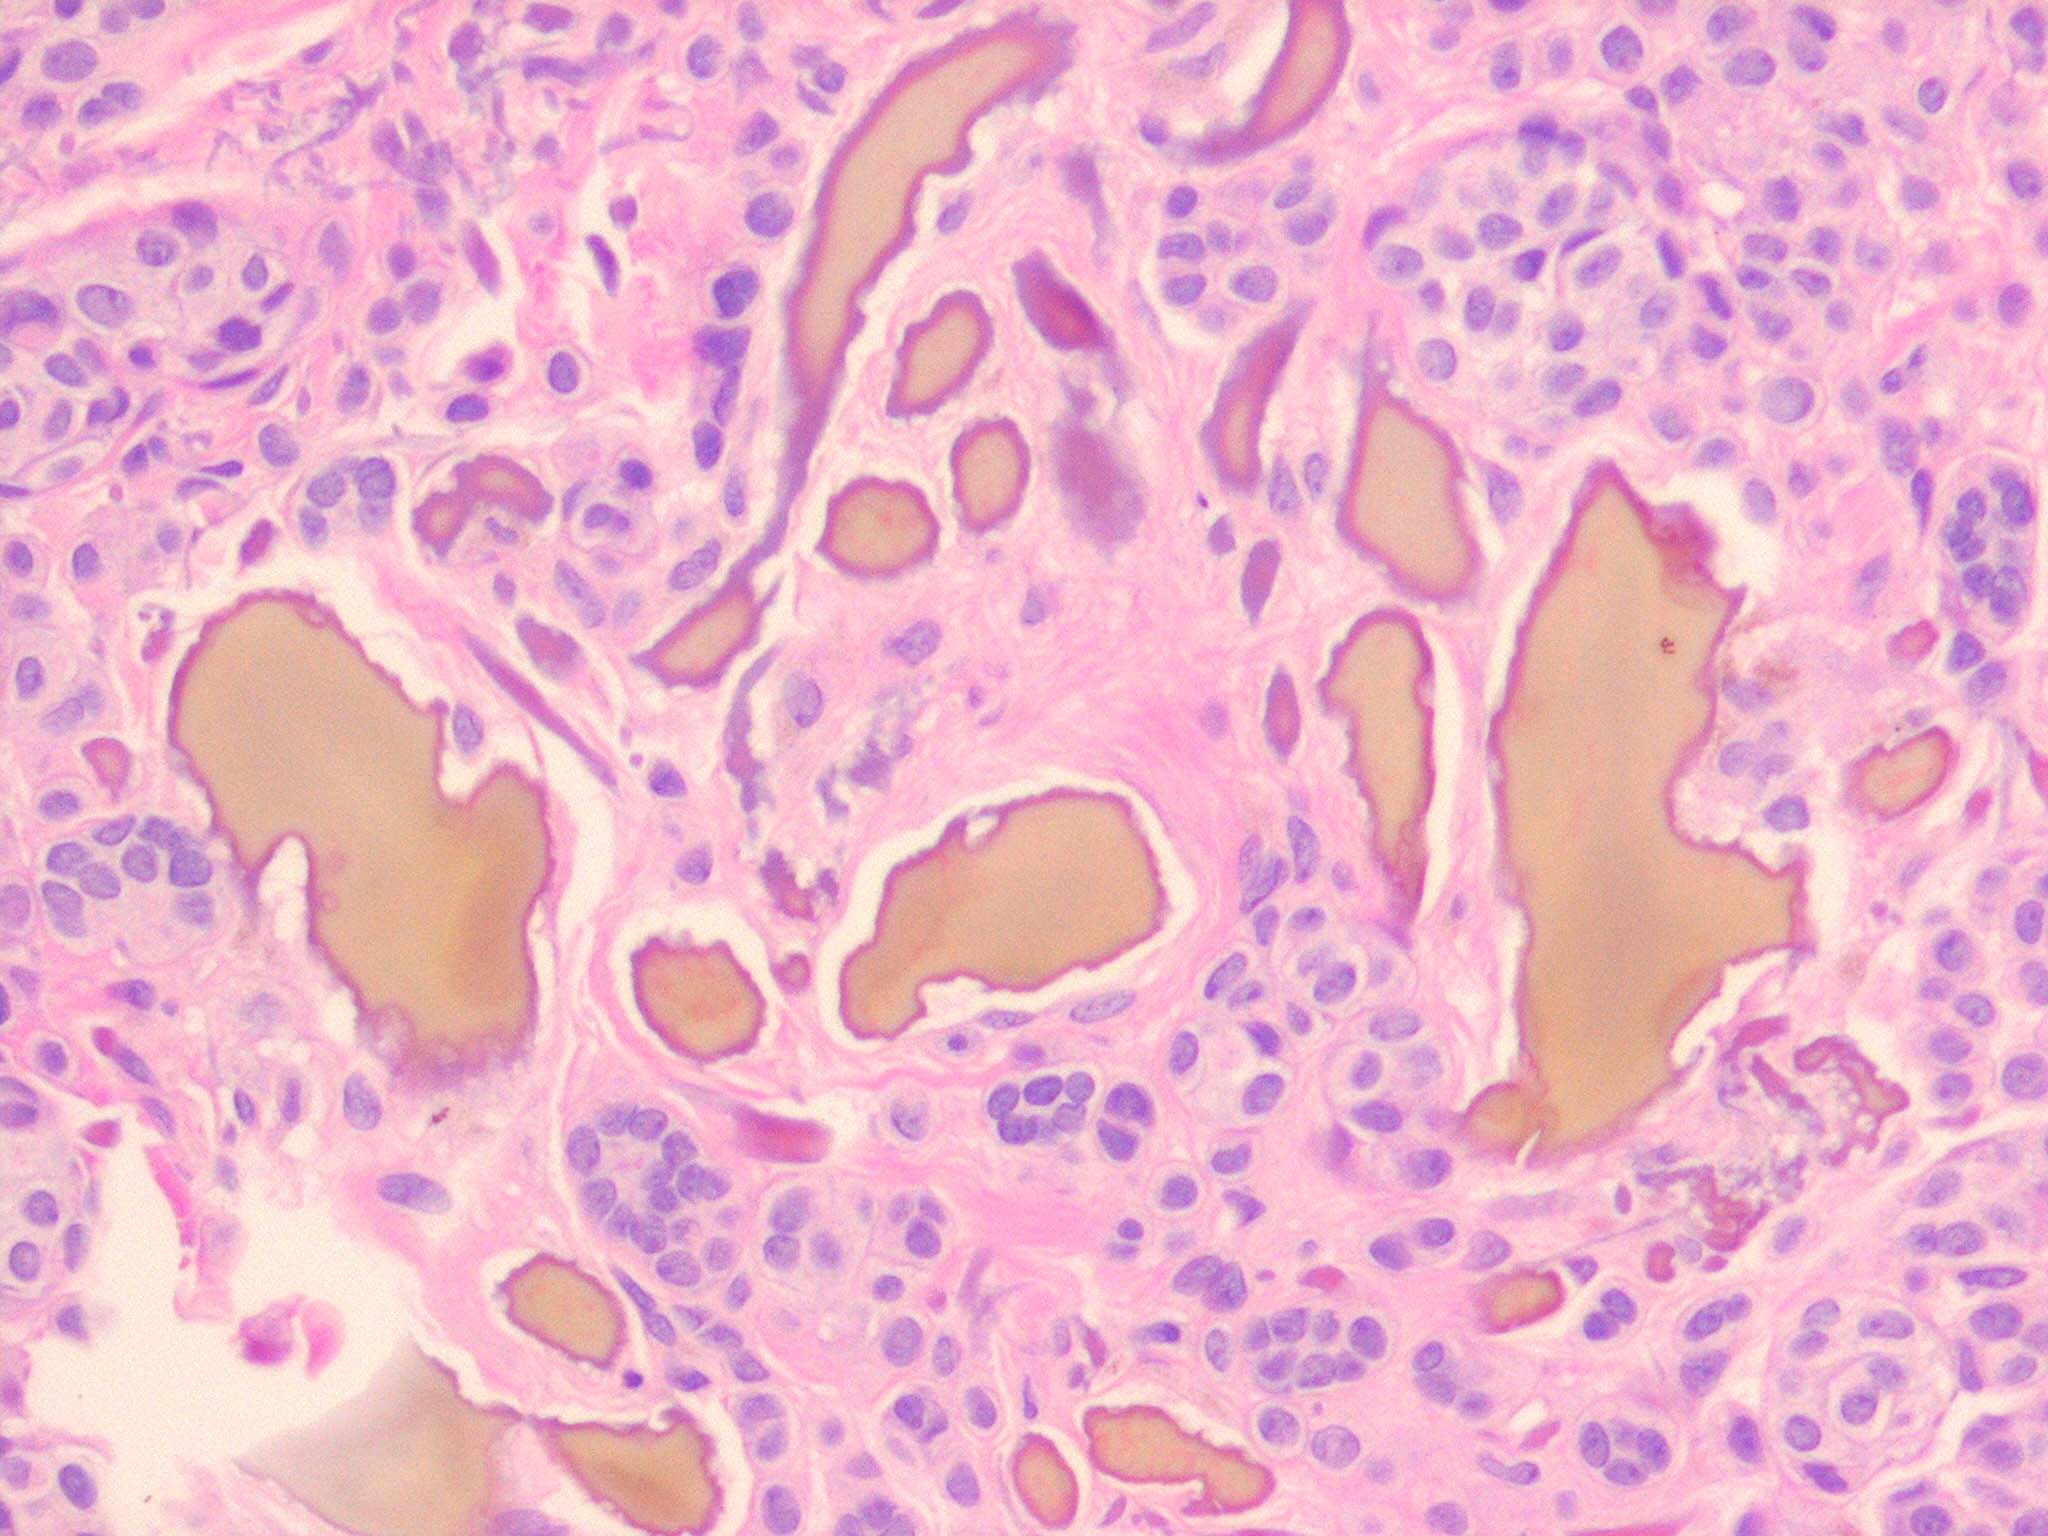

HistopathologyInvolvement of the skin is essentially identical in endogenous and exogenous ochronosis, although it is often more pronounced in exogenous ochronosis . The ochronotic pigment, as seen in sections of the dermis stained

with H&E, has a yellow-brown or ochre color; thus, the name ochronosis.

The skin shows ochronotic pigment as fine granules free in the tissue and in the endothelial cells of blood vessels, in the basement membrane and the secretory cells of sweat glands, and within scattered macrophages . The most striking finding, however, is the ochronotic pigment within collagen bundles, causing homogenization and swelling of the bundles. Some collagen bundles assume a bizarre shape; they appear rigid and tend to fracture transversely with jagged or pointed ends . As the result of the breaking up of degenerated collagen bundles, irregular, homogeneous, light brown clumps lie free in the tissue. The altered dermal connective tissue does not stain with silver nitrate as melanin does but becomes black when stained with cresyl violet or methylene blue . In addition, ochronotic pigment can be found within elastic fibers . In nodular ochronosis, a granulomatous response surrounds this material . Transfollicular elimination of ochronotic fibers may occur in patients with severe disease .